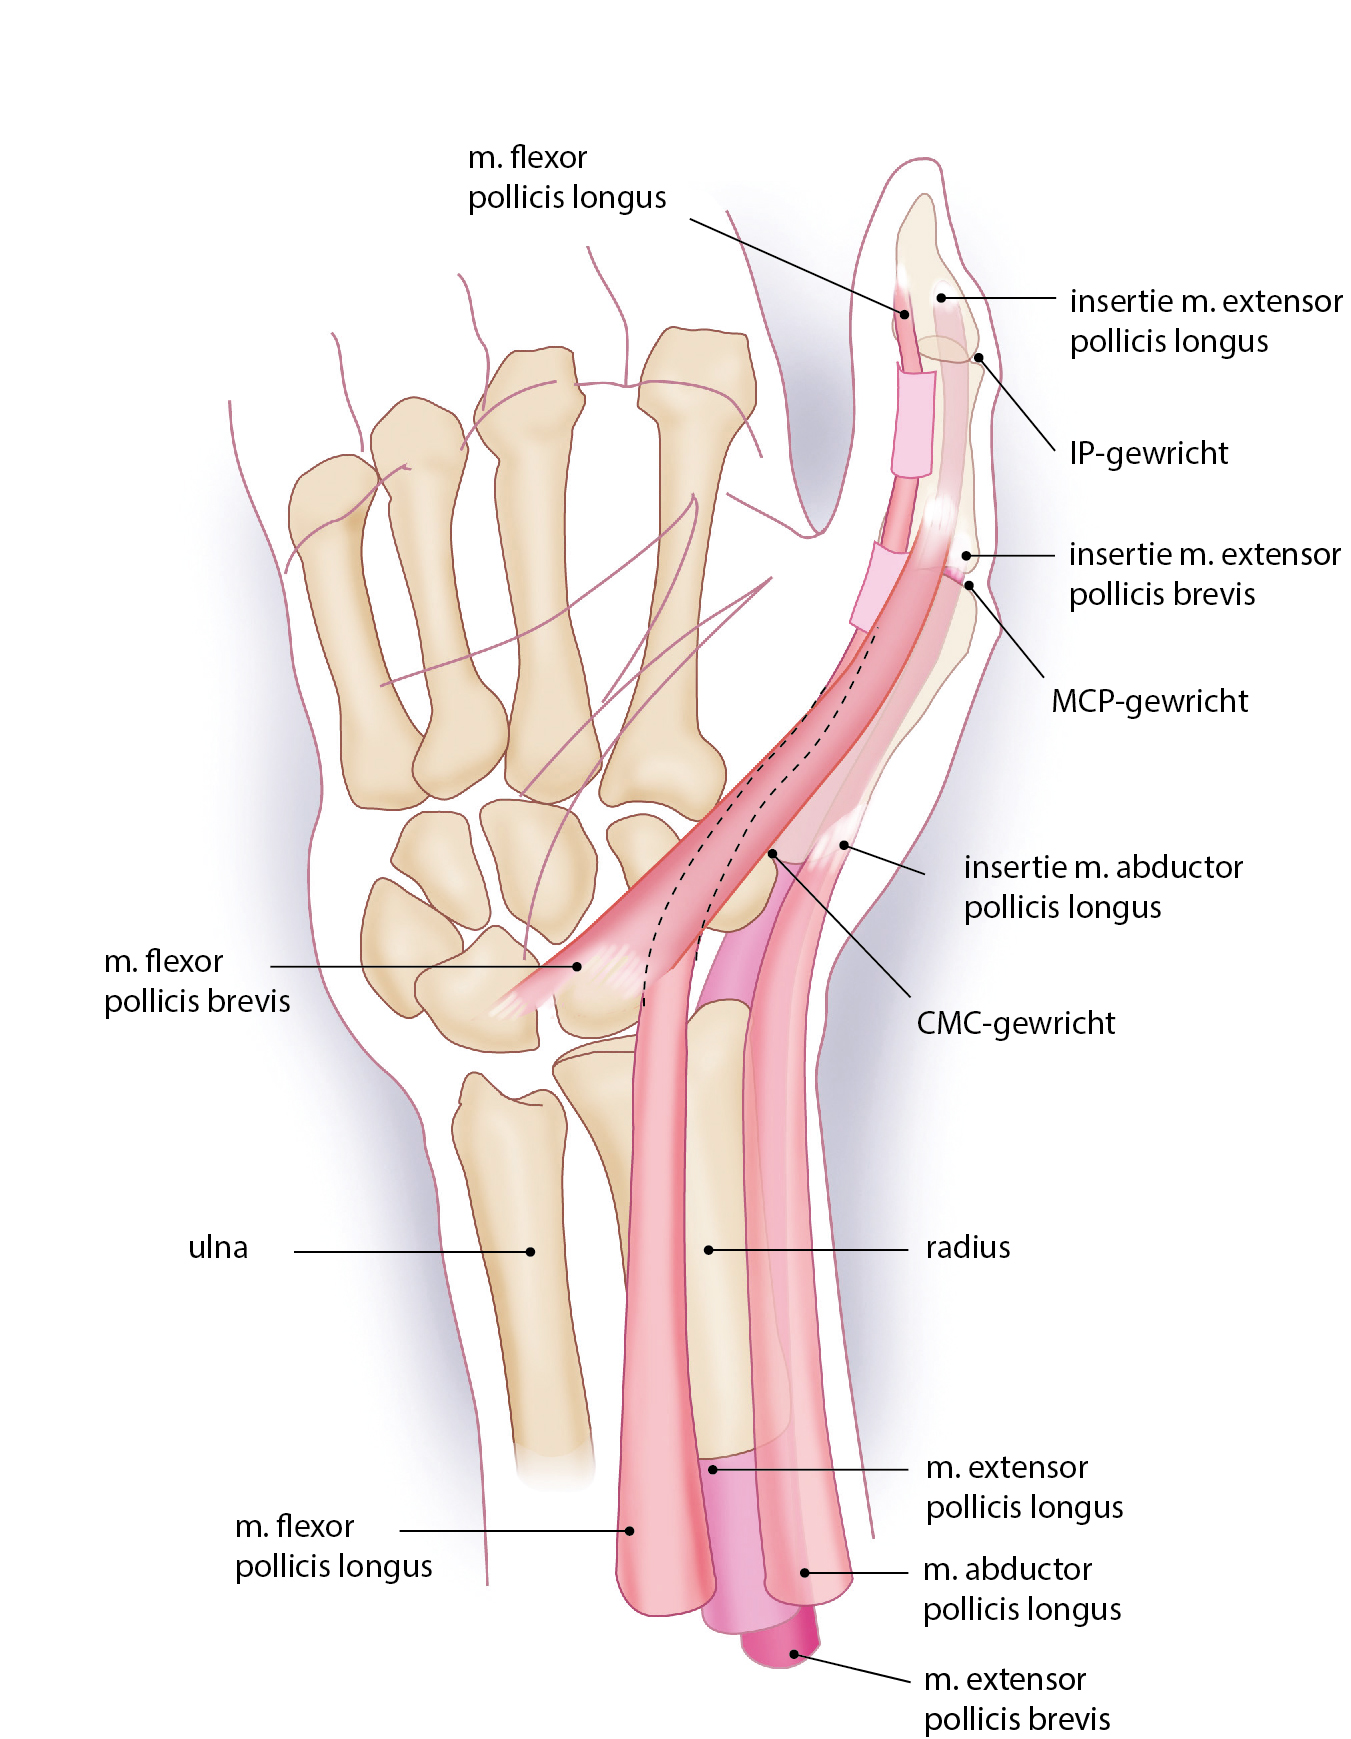

Анатомия мышцы Palmaris Longus